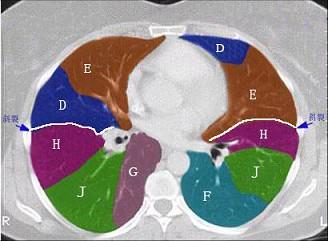

结合肺段模式(见图),选出右肺下叶的组成 ( )A.FB.F+GC.F+G+HD.F+G+H+IE.F+G+H+I+J

问题 结合肺段模式(见图),选出右肺下叶的组成 ( )

选项 A.F B.F+G C.F+G+H D.F+G+H+I E.F+G+H+I+J

答案 E